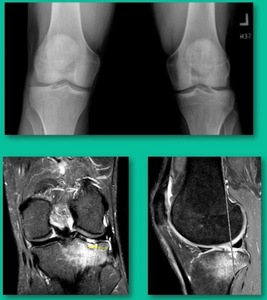

This is an 11-year-old. Left knee lateral knee pain. Effusions, the same type of classic findings (Figure 3)

You look at this one, you say, “what are you going to see when you get in there?” This is one when you get in there, you say, I’m not even sure I’m in the right knee because you almost don’t see it. That happens in patients who were painful, but they don’t look macroscopically unstable. Pediatric orthopedic surgeons tend to drill these. These are the ones that I see as failures. I think when you’re talking about something that’s mechanically unstable, it’s hard to understand why drilling would actually make it work without fixation. Even if it’s microscopically unstable.

The challenge is this. This series of patients were populated by early decisions to treat when patients don’t have symptoms. That’s a problem in my mind. Post-Op, they protect their weight-bearing. That’s actually treatment. These are often smaller lesions of the medial femoral condyle. They do really well. That being said, it’s an option. It’s not my option. My option for someone who’s macroscopically unstable is we use biocomposite screws (Figure 4).

Another case example. 14-year-old male tennis player, 10 months of knee pain (Figure 7A).

This is a Trochlear defect (Figure 7B).

Now, we’ll shift to the adult. This is a 27-year-old. Right knee swelling, activity-related, and classic failed nonsurgical treatment on the lateral side of the knee.

This will probably be fixed. It’s a big piece and we’ll try to preserve it. The literature shows that preservation does pretty well. In this instance, there’s very little bone. It’s somewhat dystrophic, not very encouraging in my mind.

This is an 18-year-old with a lateral femoral condyle OCD:

Worsening over the last two years, has effusions but no locking, and has a large area of involvement that appears unstable. This is the classic fixation. If you can do this, this is the holy grail. Remember, fracture non-union: you elevate it, debride the base, get rid of any unstable fragments, just take them out, and preserve the major fragment. I’ll use a microfracture awl, but most commonly now I’ll use a pick or a pin, and I’ll drill it. I use two to three metal screws. I bury their heads, and then I come back at eight weeks after being non-weight-bearing, and pull the screws out.